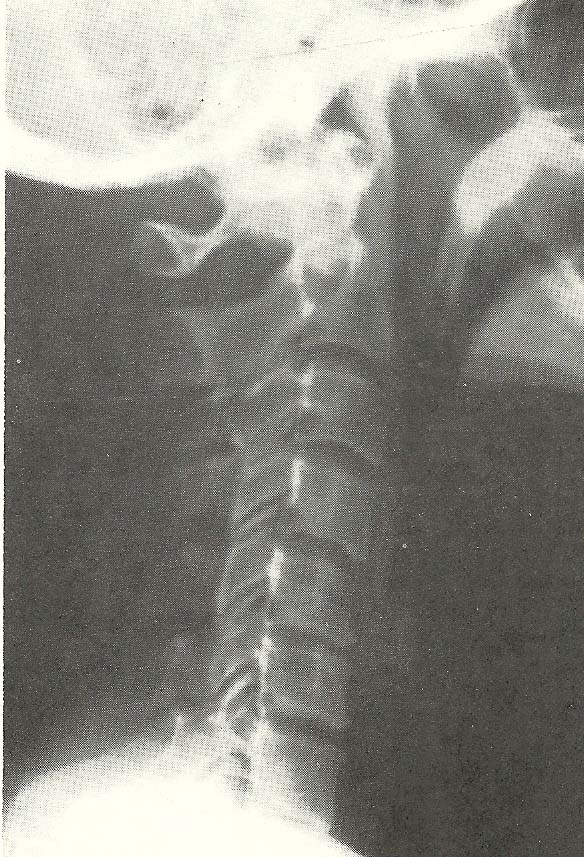

Cervical spine films revealed several abnormalities. Significant

noted. Several subluxations are apparent on the neutral lateral film alone

(Fig.  6.51). C2 shows slight anterior displacement upon C3, with C4 (A-5)

showing more anterior disrelationship relative to C5. C5 shows posterior

displacement upon C6 (A-6). The anterior carriage of the head alters the

cervical lordosis.

The lateral film taken during flexion of the neck fails to reveal

significant overall reduction in flexion, but a little flexion is seen at the

atlanto-occipital motion unit (Fig. 6.52). The anterior disrelationship of C2

upon C3 and C4 on C5 is not significantly altered during flexion, but the

posterior disrelationship of C5 upon C6 is improved.

General extension of the neck is adequate with all motion units extending

to the greatest degree allowed by structure (Fig. 6.53). In hyperextension,

there is no apparent alteration of the anterolistheses at C2-C3 and C4-C5, but

the retrolisthesis at C5-C6 is exaggerated as compared to the position in the

neutral lateral film.

The open-mouth A-P film is essentially unremarkable, but the A-P of the

lower cervical region (Fig. 6.54) shows considerable proliferative change of

the posterior facets at C4-C5 on the right and less hypertrophy at other

levels.

The oblique films (Fig. 6.55) show encroachment of the neural foramina at

C3-C4, C4-C5, C5-C6, and C6-C7 on the left with similar changes on the right

due to the uncovertebral arthrosis and uncinate hypertrophy (A-9).

In summary of the cervical spine x-ray findings, we note generalized

osteoporosis and spinal degenerative disease of moderate severity. The

subluxations observed were:

(1) Anterolisthesis at C2-C3 and C4-C5 (A-5). Note that these are not the usual spondylolistheses seen in the lumbosacral area that show defects in the pars interarticulari. These anterolistheses are allowed by the disc and articular degenerative changes. They do not change significantly in flexion or extension of the neck.

(2) Retrolisthesis at C5-C6 (A-6), which is somewhat unstable and shows moderate hypermobility and abnormal motion on neck flexion and extension.

(3) Foraminal alteration or encroachment (A-9) at nearly every level in the neck bilaterally due to degenerative change and malposition of the vertebrae.

(4) Decreased interosseous spacing (A-8) from disc degeneration.

(5) Aberrant motion (B-3) with various motion abnormalities seen on stress study.